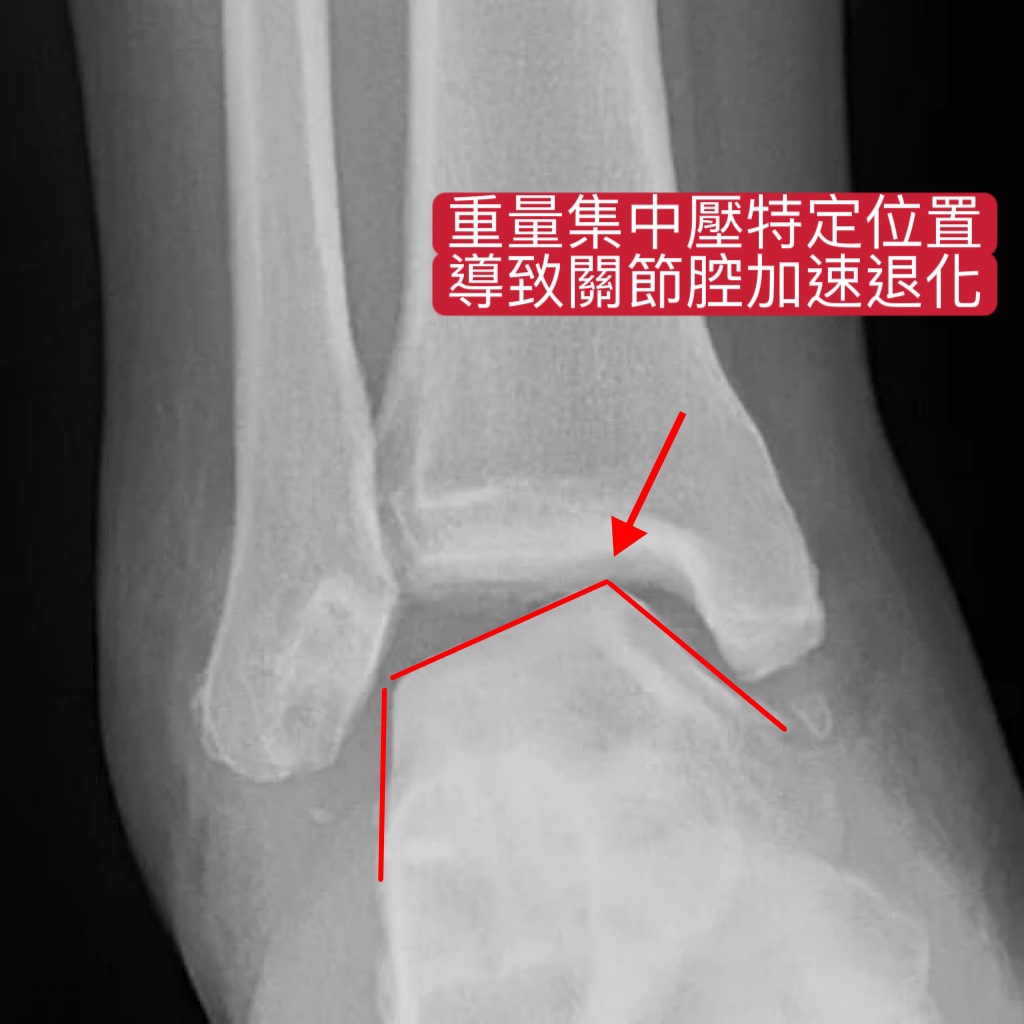

然而,若因反覆扭傷造成韌帶鬆弛、關節不穩定,行走時的重量集中壓在特定位置,導致該處軟骨加速退化(圖二)。因此患者在長時間行走後,常腳踝痠痛及容易腫脹不適感。